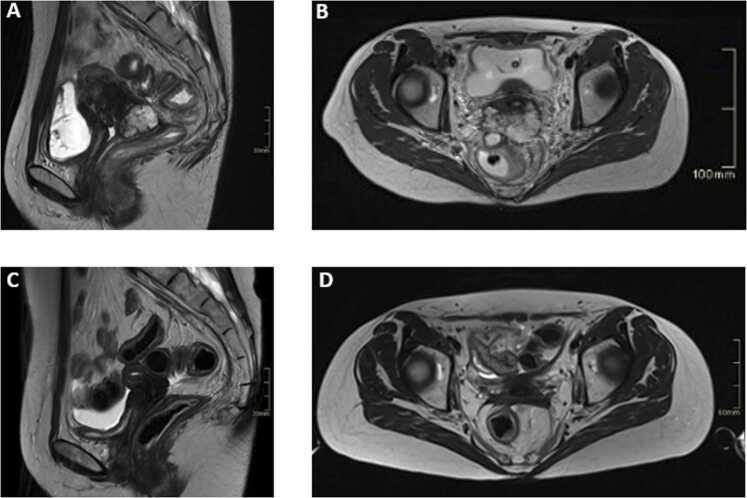

宫颈透明细胞腺癌是一种罕见的侵袭性宫颈癌亚型,通常对常规放射治疗有抗性,缺乏专门的治疗指南。我们报告了一位年轻的患者,患有共济失调毛细血管扩张突变和局部晚期疾病,在标准放化疗后不适合近距离治疗,随后接受了碳离子放射治疗。这种混合光束策略具有良好的耐受性,并导致持久的局部控制和节点响应,这表明可能存在抽离效应。这些发现强调了碳离子放射治疗在克服放射耐药方面的潜力,并提示遗传背景在介导全身免疫效应方面发挥了重要作用。

Clear cell adenocarcinoma of the uterine cervix is a rare and aggressive subtype of cervical cancer, typically resistant to conventional radiation therapy and lacking dedicated treatment guidelines. We present the case of a young patient with an ataxia telangiectasia mutation and locally advanced disease, who was unfit for brachytherapy following standard chemoradiotherapy and subsequently received a carbon ion radiation therapy boost. This mixed-beam strategy was well tolerated and led to durable local control along with a nodal response, which is suggestive of a possible abscopal effect. These findings underscore the potential of carbon ion radiation therapy in overcoming radioresistance and suggest a contributory role of genetic background in mediating systemic immune effects.